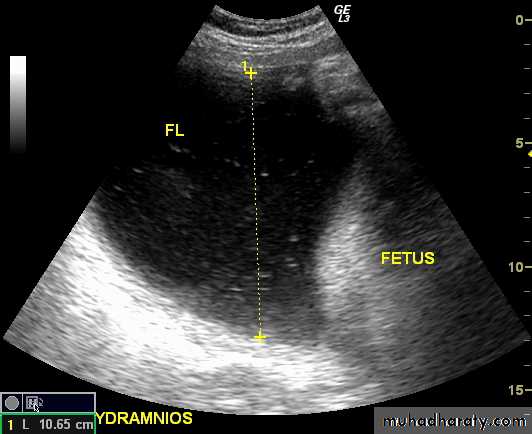

Poly hydraminous

Poly hydraminos refers to a situation where the amniotic fluid volume is more than expected for gestational age.

It is generally defined as:

amniotic fluid index (AFI) > 25 cm

largest fluid pocket depth (maximal vertical pocket (MVP)) greater than 8 cm

overall amniotic fluid volume larger than 1500-2000 cc3